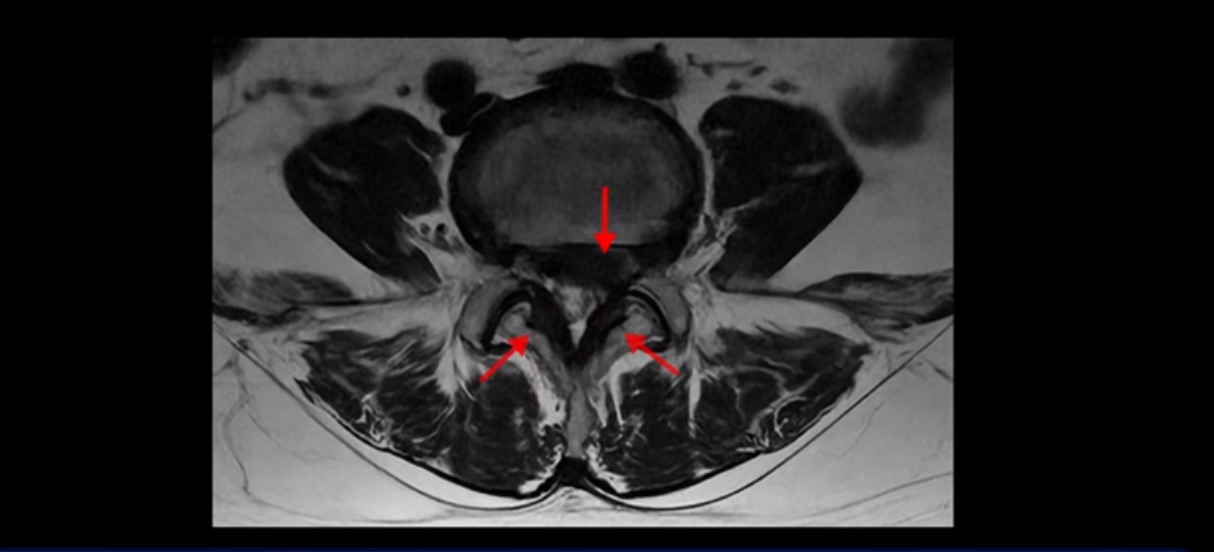

단면을 보면 디스크 수핵은 왼쪽으로 심하게 밀려 나와 있고

좌우 뒤쪽에는 황색 인대가 두꺼워져 있습니다.

앞에서는 디스크 수핵이 신경 공간으로 침범하고 뒤에서는 두꺼워진 인대가 신경 공간을 좁히고 있습니다.

이렇게 신경 공간이 좁아진 것을 협착이라고 합니다. 왼쪽으로 신경 구멍이 더 좁아져 있으니까 처음에는 왼쪽 엉덩이와 다리가 아팠는데 몇 년 동안 주사 맞으면서 버티다 보니까 오른쪽 다리까지 아프게 됩니다. 결국 양쪽 다리가 너무 아파서 5분 걷기도 힘들어지게 됩니다.